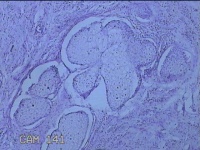

面部、下颌肿物

性别

女

年龄

36岁

临床诊断

皮脂腺囊肿

一般病史

无

标本名称

大体所见

灰白暗红色带皮肤样肿物1.3x0.8x0.3cm一个,表面光滑,起开肿物呈实性,切面灰白暗红色,质软。